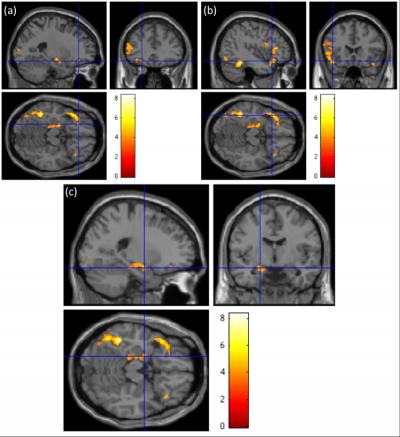

The researchers found that the sentences containing words that invoked taste activated areas known to be associated with emotional processing, such as the amygdala, as well as the areas known as the gustatory cortices that allow for the physical act of tasting. Interestingly, the metaphorical and literal words only resulted in brain activity related to emotion when part of a sentence, but stimulated the gustatory cortices both in sentences and as stand-alone words.